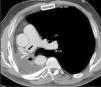

Corte axial de tomografía computarizada multidetector tras contraste intravenoso en fase arterial, en paciente con antecedente de neumonectomía derecha. Se observa defecto de repleción compatible con trombosis del muñón arterial (flecha negra) y también se aprecian las suturas asociadas a la misma (flecha blanca).